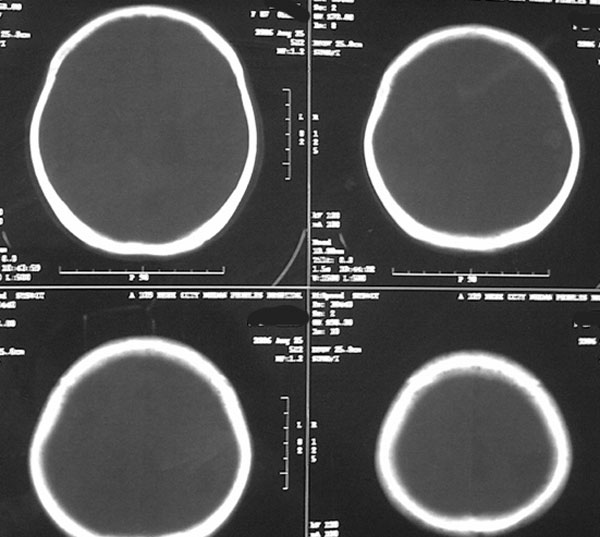

女87左下肢麻木,无外伤史

右颞顶部颅骨内板下新月形混杂密度影,右大脑皮层受压内移,考虑慢性硬膜下血肿,建议增强一下看看病灶,因为平扫好像显示的不是很好;左顶部软化灶

右侧大脑半球脑沟 脑裂变浅或消失,顶叶不规则低密度影,右侧侧脑室明显受压移位,中线偏移,右侧内板下新月形混杂高密度致密影,多考虑:慢性硬膜下血肿.必要时建议强化扫描.

右额颞顶部颅骨内板下方新月形混杂密度影,同侧灰白界限受压内移,右侧脑室呈受压性改变,中线结构左移;左顶叶扫及片状脑脊样低密度区,另可见部分脑沟增宽

ct印象:1.右额颞顶部慢性硬膜下血肿

2.左顶叶软化灶

3.脑部分萎缩